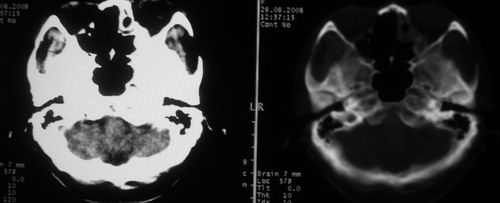

女,55岁,右侧颌下肿物3年。

右侧胸锁乳突肌后方软组织密度肿块,界限清楚。多考虑:血管源性肿瘤!

鼻咽左侧壁增厚,呈结节样突入鼻咽腔内,左侧咽隐窝消失,须考虑鼻咽癌可能,建议鼻咽纤维镜检查以明确诊断。

至于右侧颌下间隙的结节影,如果不考虑病史的话,可以诊断为淋巴结转移。但是结合病史“右侧颌下肿物3年”,又不象淋巴结转移了。建议ct增强扫描明确结节与右侧颌下腺的关系,或者穿刺活检定性。

右侧胸锁乳突肌内侧略低密度结节,应该是静内静脉而不是淋巴结。